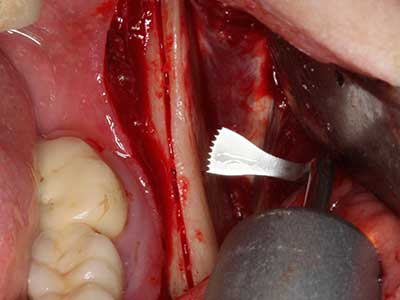

Si es preciso realizar intervenciones quirúrgicas en las que el hueso está en contacto directo con estructuras sensibles, como son los vasos sanguíneos o los nervios, los instrumentos rotativos presentan un enorme potencial de provocar lesiones iatrogénicas. Así, precisamente en la representación de nervios después de una lesión iatrogénica, o en el transcurso de la lateralización de un nervio para resecciones, reconstrucciones o incorporación de implantes, los equipos piezoeléctricos pueden resultar muy útiles para preparar la tapa ósea y retirar las partes de tejido duro cercanas al nervio (fig. 17-20). Por lo general, un ligero contacto del cordón nervioso con el inserto piezoeléctrico no tiene consecuencia alguna; ahora bien, un procedimiento poco cuidadoso con movimientos tipo sierra o piezas de trabajo sobre la base ósea aún existente puede provocar lesiones nerviosas temporales o incluso permanentes. Con todo, el riesgo de sufrir una lesión de este tipo se considera significativamente inferior que en los casos en los que se utilizan sierras y fresas (Pereira, Gealh et al. 2014).

Fig. 18: Preparación de una tapa cortical con la sierra ósea piezoeléctrica (Piezomed, W&H).

Fig. 19: Zona operada después de neurolisis y eliminación del osteomo.

Fig. 20: La tapa ósea extraída se readapta y se fija mediante un tornillo para osteosíntesis (KLS Martin, Tuttlingen).